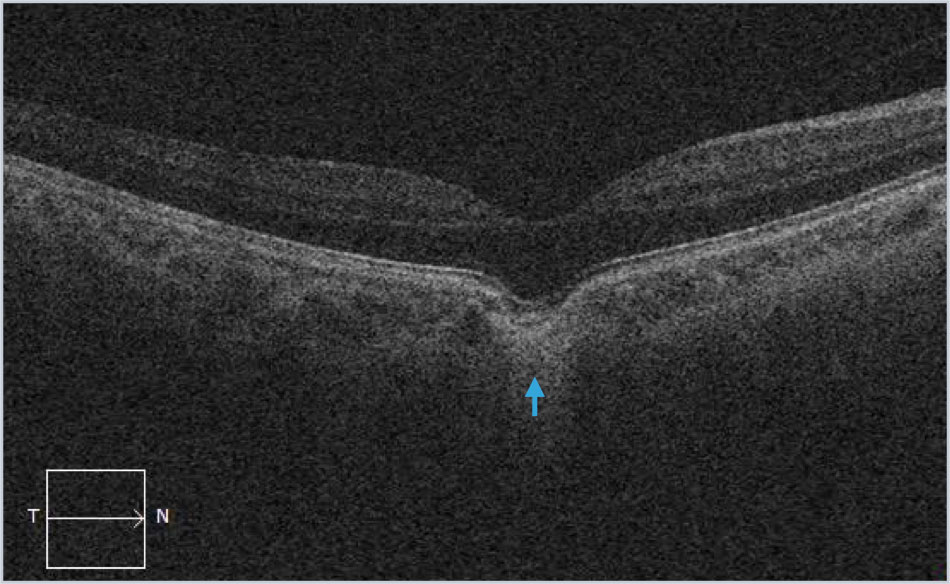

Focal choroidal excavation is commonly abbreviated as FCE and can be noted incidentally as well as in patients with an antecedent history of inflammatory chorioretinal disease.

Examples (blue arrows) from different patients with focal choroidal excavation. This finding is often noted incidentally and patients rarely have symptoms. Occasionally it can be associated with macular neovascularization and inflammatory disorders. The key visual sign on SD-OCT imaging is the outward bowing of the RPE.